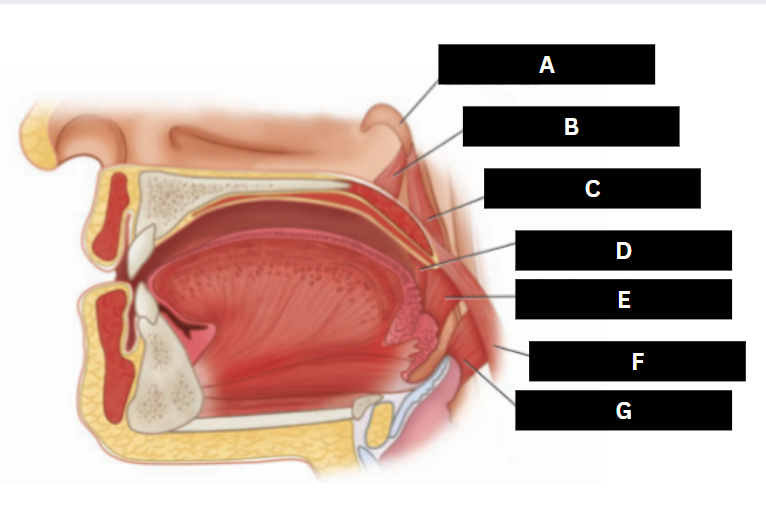

Eustachian tube

A

Levator veli palatini

B

Salpingopharyngeus

C

Palatoglossus

D

Superior pharyngeal constrictor

E

Palatopharyngeus

F

Middle pharyngeal constrictor

G